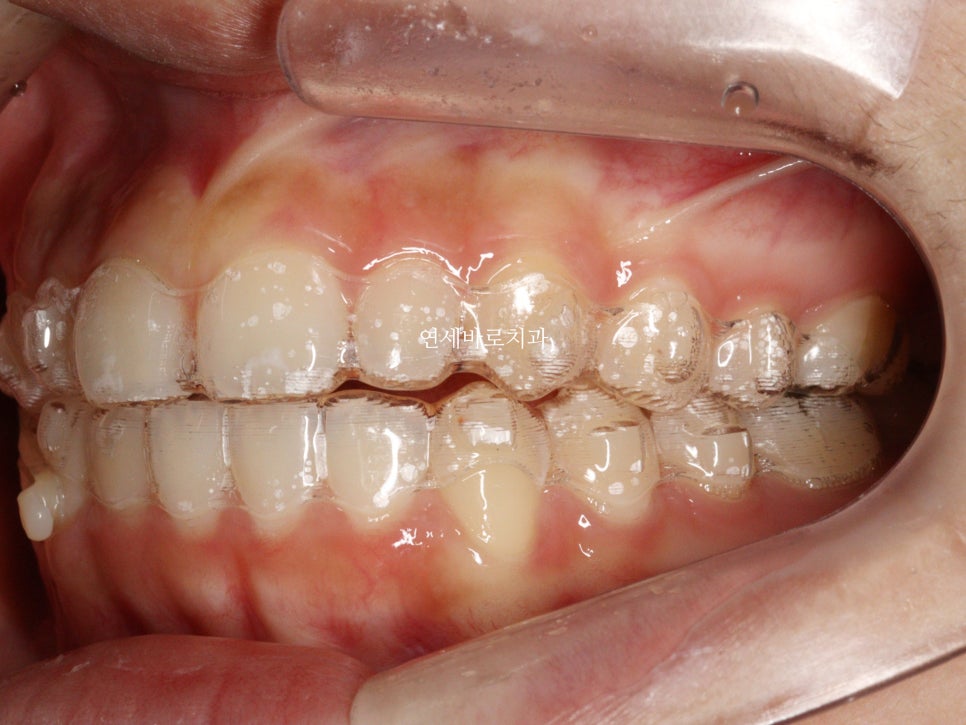

치료가 끝난 당시 모습입니다.

앞니가 듬성듬성 벌어진것이 보기 아쉽네요

이렇게 된 이유는 두가지

왜소치

앞니 형태가 항아리모양 (네모가 아님)

이 문제를 해결하기 위해서는 무삭제라미네이트를 추천합니다.